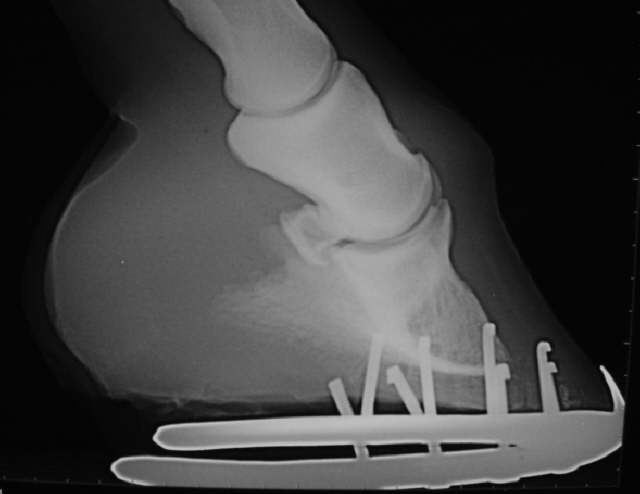

Bockhuf mit deutlicher Atrophie der Hufbeinspitze.